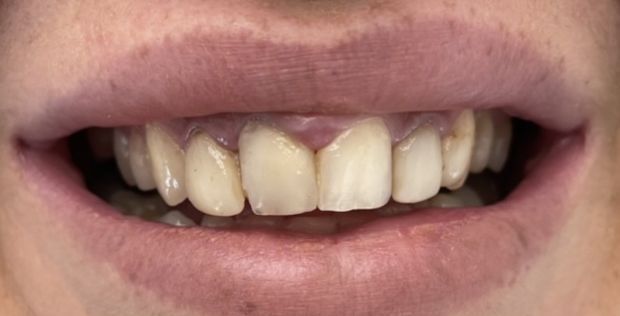

Licówki pełnoceramiczna wykonane cyfrowo w systemie CAD/CAM w przypadkach, kiedy poprawiamy estetykę – kształt i kolor zębów.